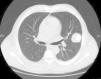

The new chest computed tomography (CT) at the 3-month check-up (Fig. 1) showed that the mass in the LUL had increased in size (4.9×4.1cm), so surgical resection of the pulmonary mass was performed. Based on the pathology report, diagnosis was metastatic chondrosarcoma. Biopsies from the palatal tumor resected 12 years previously were reviewed, and the conclusion was made that it had been a mixed tumor type, with a double epithelial and mesenchymal component. The epithelial component was small and benign. The malignant component was a mesenchymal chondrosarcoma.